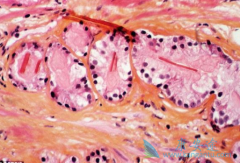

基于蛋白表达(免疫组化等检测)、mRNA表达(RNA-seq等检测)等多组学的免疫微环境相关的分子标志物已经在进行研究,如基于CD8A mRNA表达或CD8免疫组化的TILs水平联合PD-L1蛋白表达水平可更好地筛选响应 免疫治疗 的患者。   IFNγ等炎症反应相关基因 ...

PD-L1蛋白表 达反映的是肿瘤组织中潜在的PD-1/PD-L1药物作用靶点,而MSI-H和TMB-H一定程度上能反映患者肿瘤新抗原的数量。为什么PD-L1表达阳性和TMB-H的患者响应PD-1/PD-L1抑制剂仍不理想呢?研究发现其中部分原因可能和肿瘤的免疫微环境有关,当中最重 ...